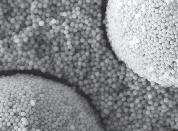

Kan tydeligt ses på SEM-billedet: Perlestrukturen i OMNICHROMA sammenlignet med konventionelt knuste partikler.

Smart Chromatic Technology –1.000 hvide farver

Strukturelle farvenuancer uden kunstige farvepigmenter: tilpasser sig uden problemer til enhver tandfarve fra A1 til D4

Bis-GMA-fri formel: for bedre biokompatibilitet

Enkel lagerføring: blot 1 farve er nok til økonomisk bæredygtighed

Vareprøver & Mere tokuyama-dental.eu